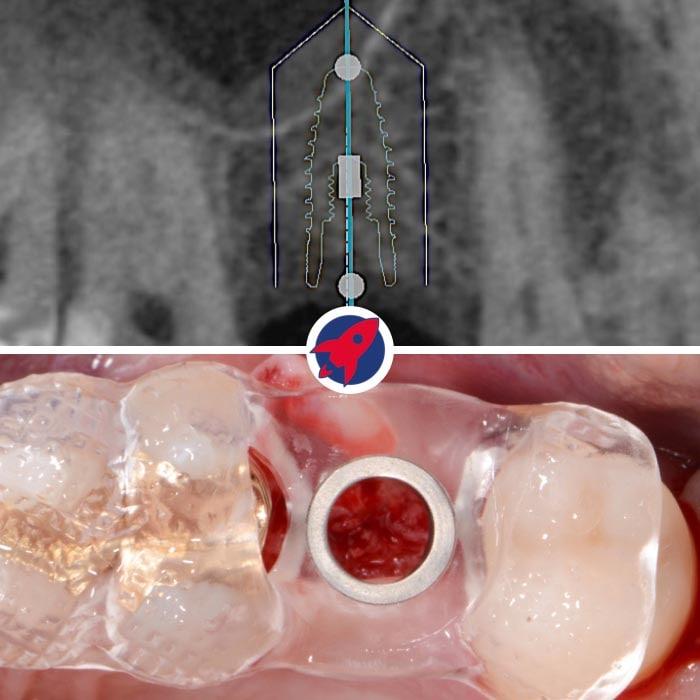

Digitale Planung & Schablonenfertigung

Basierend auf den DVT-Daten (Bild oben) erstellen wir die exakte Position, Länge und Neigung des Implantats am Computer. Bei Bedarf fertigen wir eine hochpräzise Bohrschablone an (unten).

Planung eines Zahnimplantats mittels 3D-Bildgebung: Ein detailliertes 3D-Röntgenbild zeigt die exakte Positionierung eines Zahnimplantats im Kiefer. Die Grafik illustriert die präzise Implantatplanung mit sichtbaren Messlinien für eine passgenaue Einbringung zwischen den Zähnen.